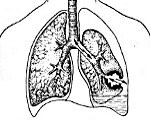

Рентгенограмма при пиопневмотораксе характеризуется смещением органов средостения в здоровую сторону, наличием одного или нескольких горизонтальных уровней жидкости (гноя) в полости плевры, над которыми определяется резко выделяющийся воздушный пузырь. При неограниченном пиопневмотораксе наблюдается частичное или полное спадение легкого, при ограниченном процессе - вытянутые веретенообразные осумкованные гнойно-воздушные полости. Разделение листков висцеральной и париетальной плевры патогномонично для пиопневмоторакса и хорошо определяется при плеврографии после контрастного усиления.